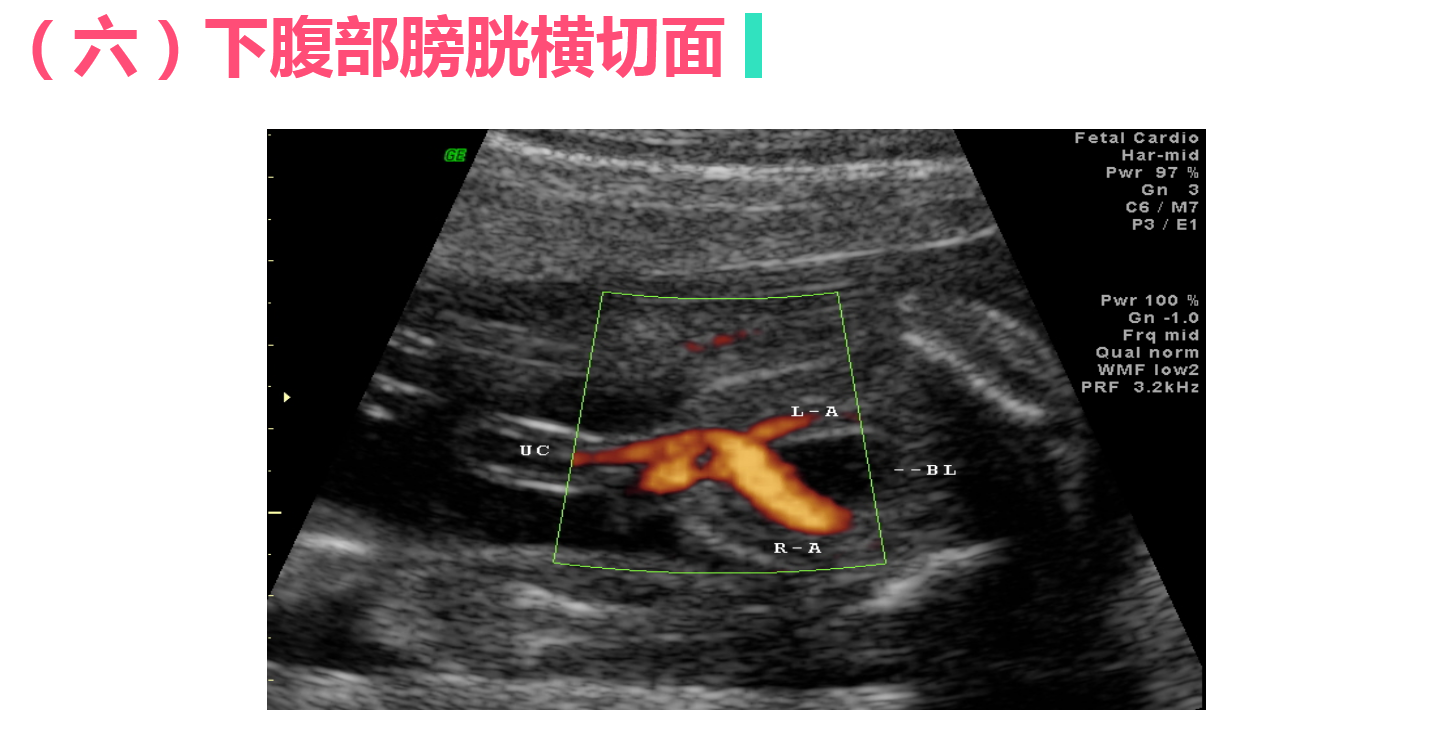

正常中晚期妊娠声像图